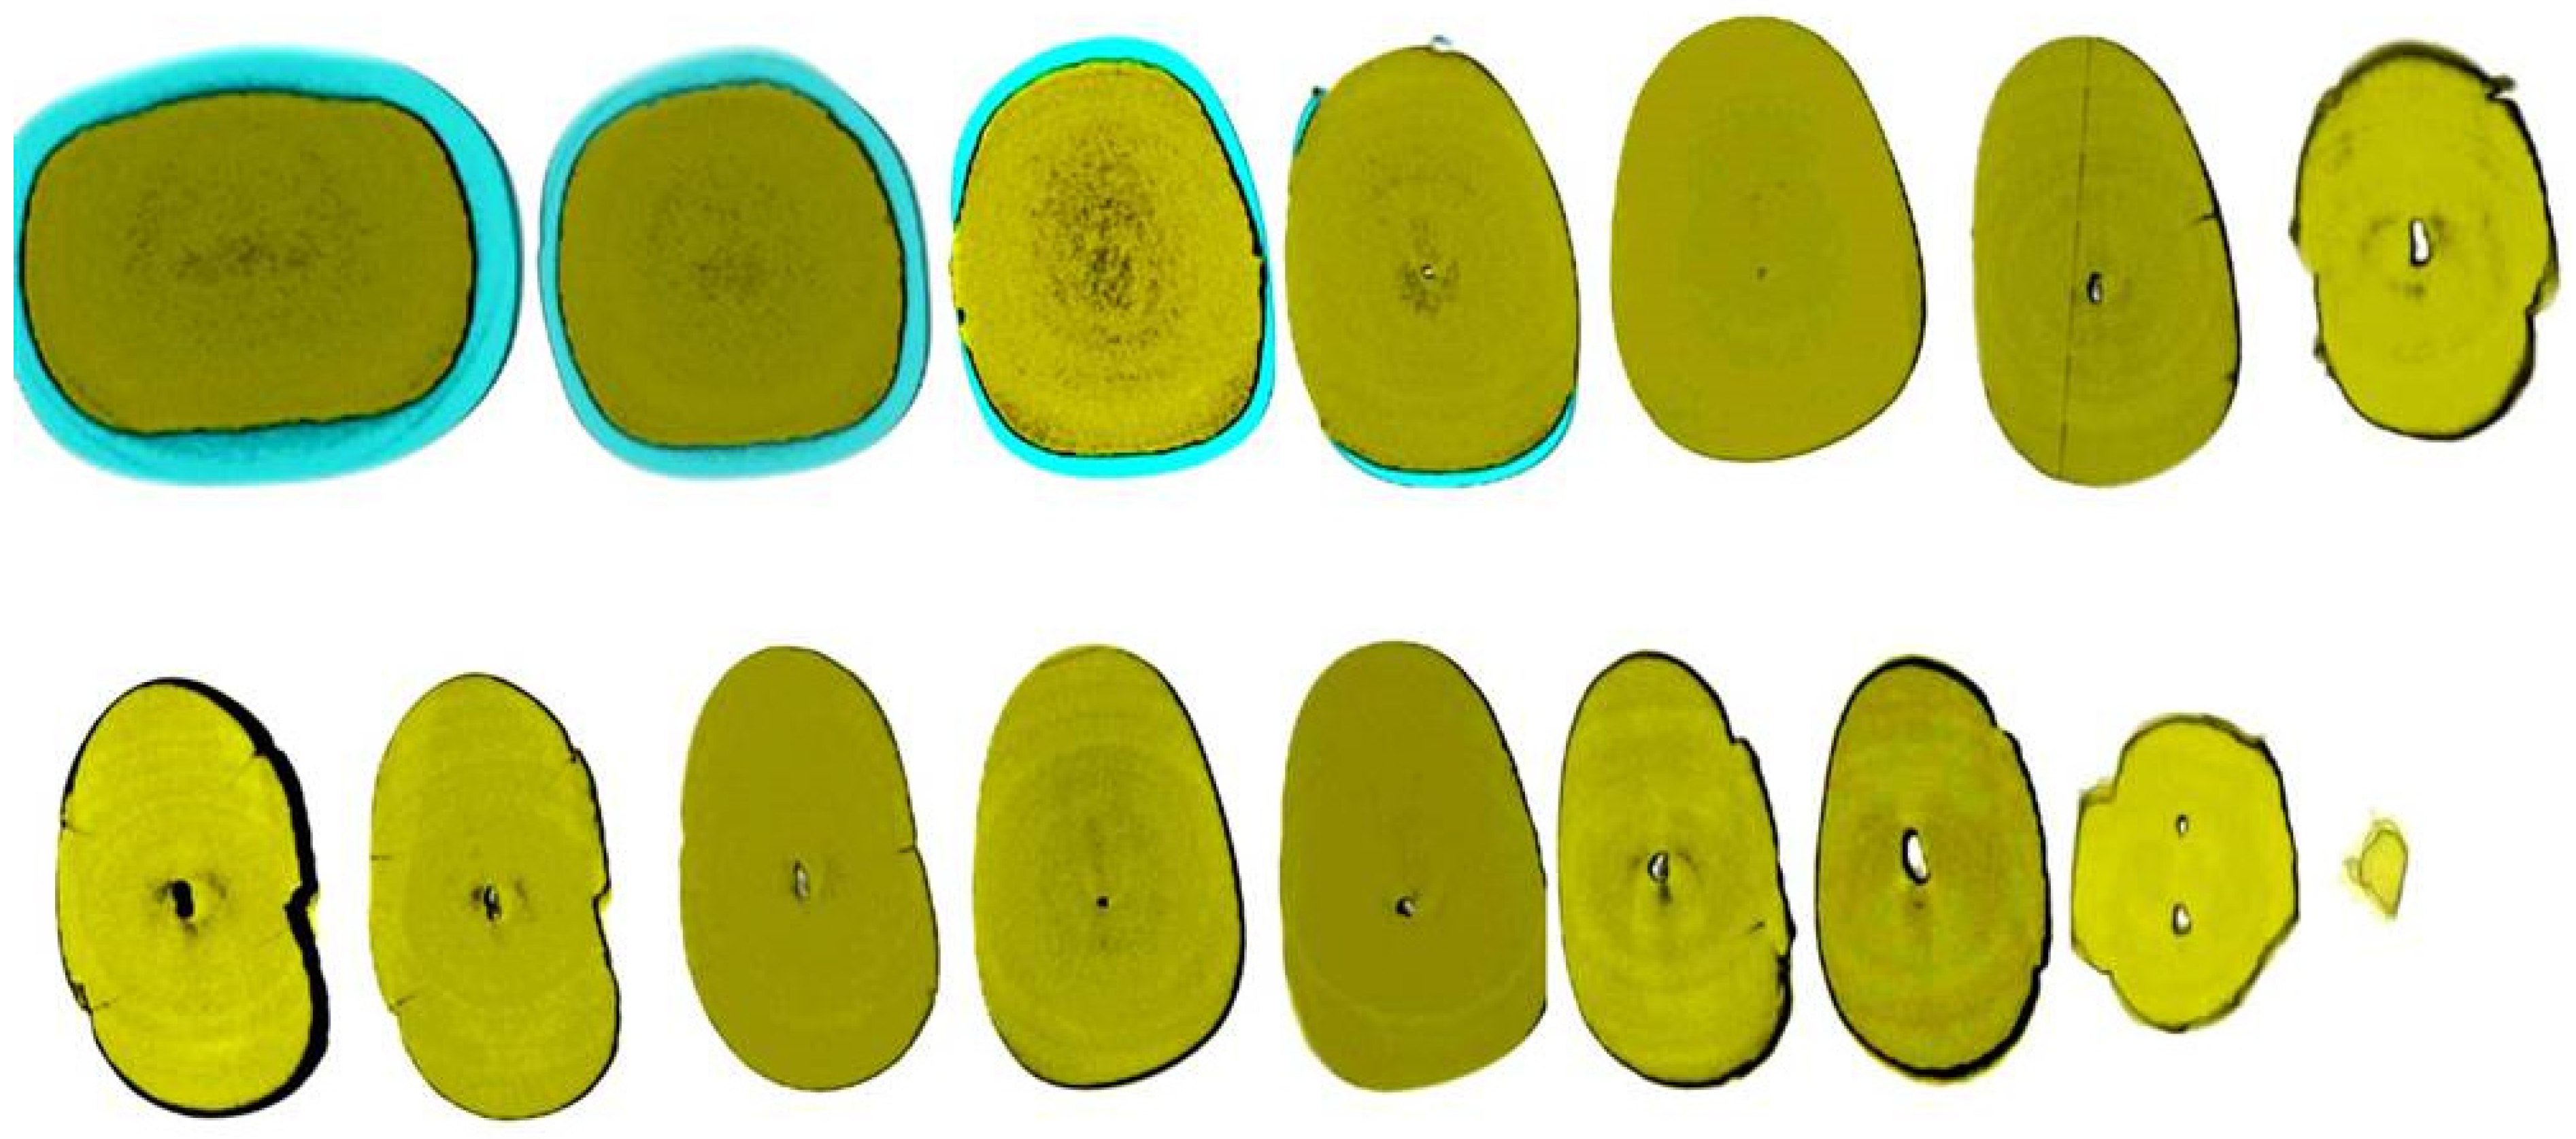

Figure 2.

Axial micro-ct slices of the calcified mandibular incisor of Figure 1 reveal the cross-sectional root canal dimensions along the root. The crown of the tooth is completely blocked, and the canal is visible starting at the level of the CEJ. The root canal dimensions are constricted along the coronal part of the root, becoming wider in the middle, followed by an apical splitting into two canals. Calcified cases usually present an inverted taper (Skyscan 1172 micro-CT scanning device, Bruker MicroCT, Belgium) (images courtesy of Dr. Alexey Volokitin, city of Dnepr, Ukraine).